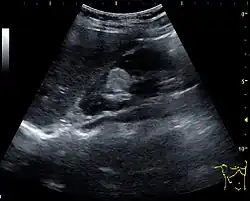

Other malignant tumors in the kidney are transitional cell carcinoma and squamous cell carcinoma, which arise from the urothelium and are found the renal sinus, as well as adenocarcinoma, lymphoma and metastases, which can be found anywhere in the kidney (Figure 10).[1]

Figure 10. Solid tumor in the renal sinus seen as a hypoechoic mass, later found to be lymphoma. The '1' and '2' on the US image are reference points used for CT fusion (not shown).[1] -